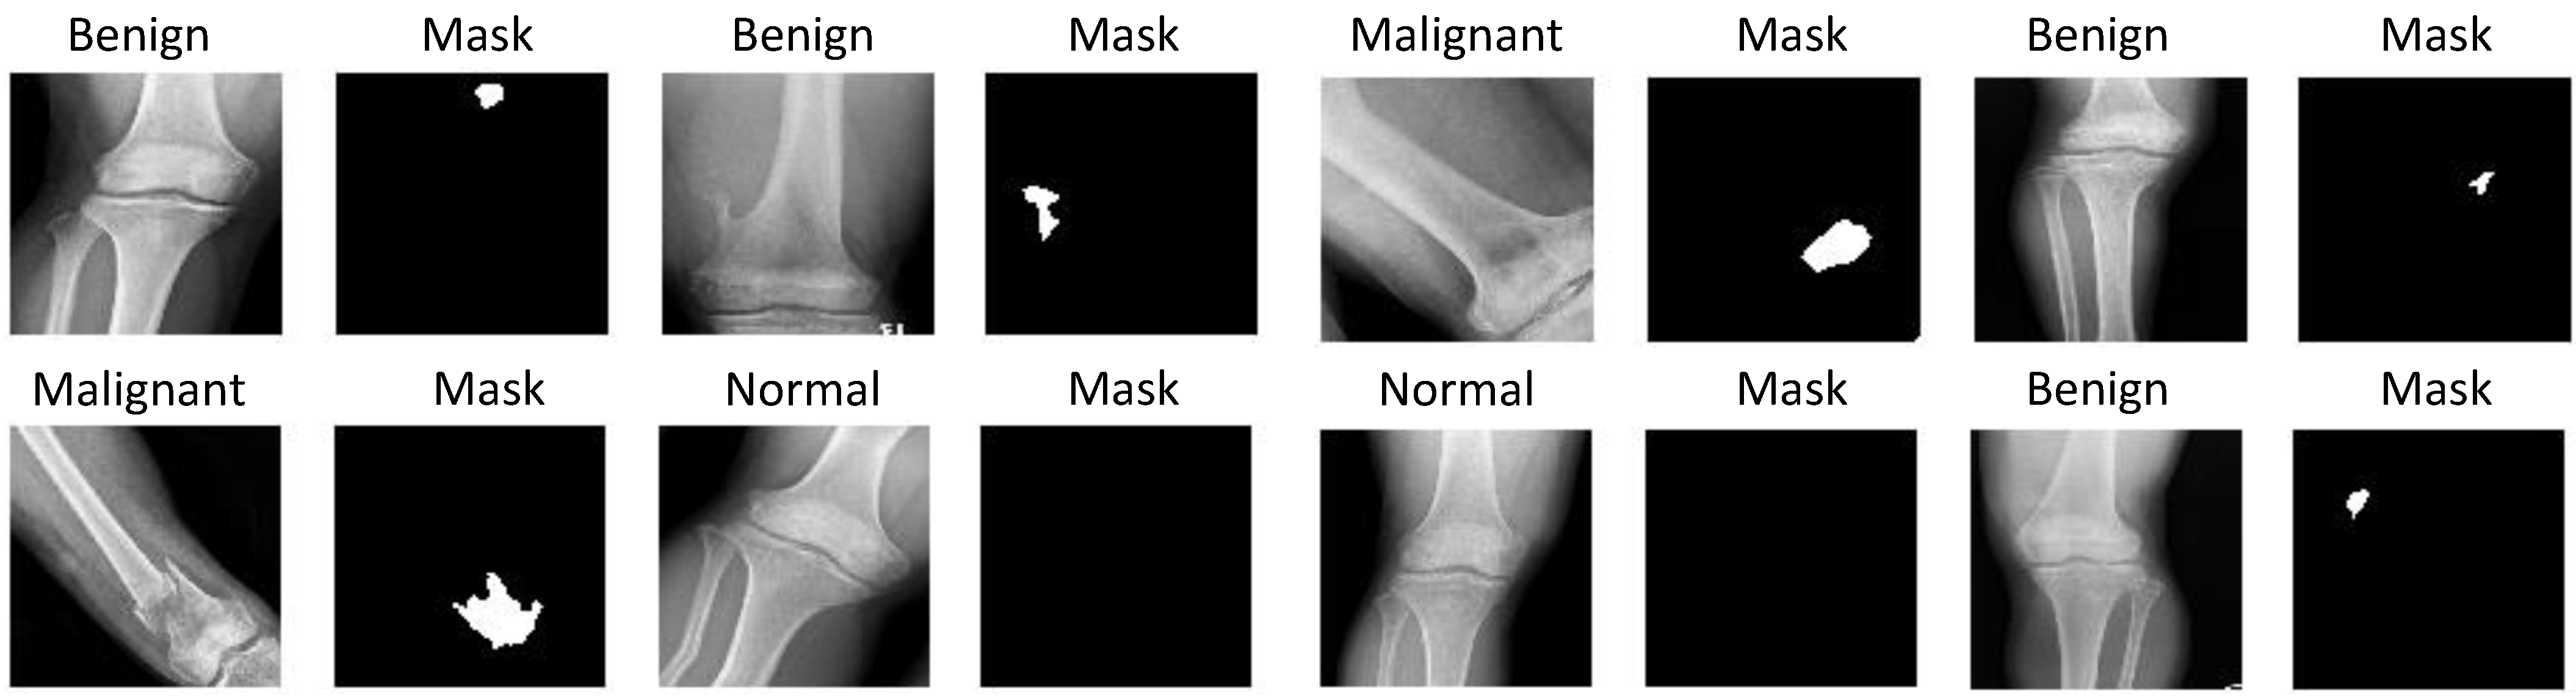

2.1. CNUH Dataset and Challenges

| Knee Region | Benign Tumor | Malignant Tumor | Normal |

|---|---|---|---|

| Distal femur | 598 | 89 | - |

| Proximal tibia | 463 | 45 | - |

| Total | 1061 | 134 | 381 |